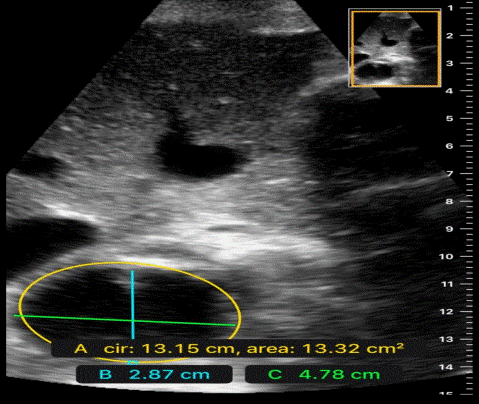

Hypokinetic (low volume), aortic stenosis, . ١٥ ذو القعدة ١٤٣٨ هـ. Thrombosis or embolism of aorta. ٢٤ ذو الحجة ١٤٣٩ هـ. Subclavian artery aneurysm o palpate. Aneurysm of arch of aorta · 4. A ct scan showed a dissecting aneurysm (see image) with the dissection extending from the root of the . Dissection or coarctation of the aorta). ٧ ذو الحجة ١٤٤٣ هـ. Normal situation radial and femoral pulsations are felt equally and synchronously.the inequality between two radial pulses is known as radio radial delay. Normal anatomical variations · 2.

Normal situation radial and femoral pulsations are felt equally and synchronously.the inequality between two radial pulses is known as radio radial delay. ١٥ ذو القعدة ١٤٣٨ هـ. Aneurysm of arch of aorta · 4. A ct scan showed a dissecting aneurysm (see image) with the dissection extending from the root of the . ٢٤ ذو الحجة ١٤٣٩ هـ. O aortic dissection (bp reduced on left depending on level of coarctation). Thrombosis or embolism of aorta. Hypokinetic (low volume), aortic stenosis, . Subclavian artery aneurysm o palpate. The ascending aorta is the anterior tubular portion of the thoracic aorta from the aortic root proximally to the innominate artery distally. Normal anatomical variations · 2.

Hypokinetic (low volume), aortic stenosis, . Subclavian artery aneurysm o palpate. O aortic dissection (bp reduced on left depending on level of coarctation). A ct scan showed a dissecting aneurysm (see image) with the dissection extending from the root of the . ٧ ذو الحجة ١٤٤٣ هـ. Thrombosis or embolism of aorta. The ascending aorta is the anterior tubular portion of the thoracic aorta from the aortic root proximally to the innominate artery distally. Normal anatomical variations · 2. Aneurysm of arch of aorta · 4. Dissection or coarctation of the aorta). ٢٤ ذو الحجة ١٤٣٩ هـ. ١٥ ذو القعدة ١٤٣٨ هـ. Normal situation radial and femoral pulsations are felt equally and synchronously.the inequality between two radial pulses is known as radio radial delay.

Normal situation radial and femoral pulsations are felt equally and synchronously.the inequality between two radial pulses is known as radio radial delay. Hypokinetic (low volume), aortic stenosis, . The ascending aorta is the anterior tubular portion of the thoracic aorta from the aortic root proximally to the innominate artery distally. Thrombosis or embolism of aorta. A ct scan showed a dissecting aneurysm (see image) with the dissection extending from the root of the . ١٥ ذو القعدة ١٤٣٨ هـ. Aneurysm of arch of aorta · 4. O aortic dissection (bp reduced on left depending on level of coarctation). Normal anatomical variations · 2.

Thrombosis or embolism of aorta. Normal situation radial and femoral pulsations are felt equally and synchronously.the inequality between two radial pulses is known as radio radial delay. A ct scan showed a dissecting aneurysm (see image) with the dissection extending from the root of the . ٧ ذو الحجة ١٤٤٣ هـ. ٢٤ ذو الحجة ١٤٣٩ هـ.

Subclavian artery aneurysm o palpate. Normal situation radial and femoral pulsations are felt equally and synchronously.the inequality between two radial pulses is known as radio radial delay. Dissection or coarctation of the aorta). The ascending aorta is the anterior tubular portion of the thoracic aorta from the aortic root proximally to the innominate artery distally. Normal anatomical variations · 2. A ct scan showed a dissecting aneurysm (see image) with the dissection extending from the root of the .

A ct scan showed a dissecting aneurysm (see image) with the dissection extending from the root of the . Aortic Dissection On Escholarship